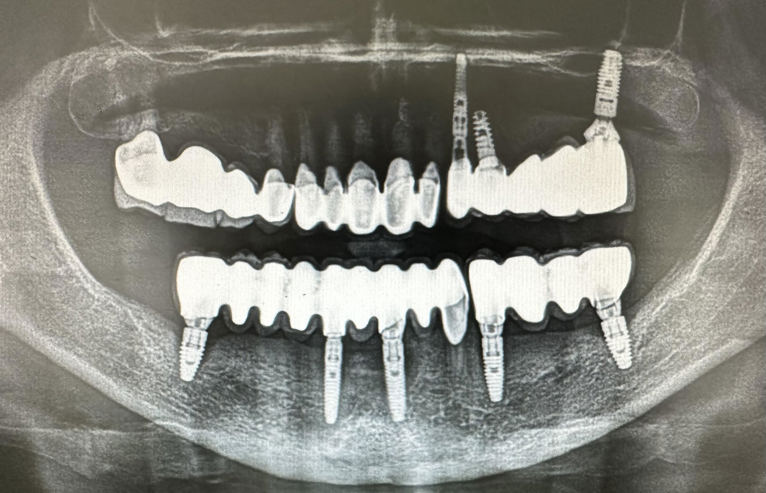

Zubni implantati su titanski vijci koji se ugrađuju u kost kao zamjena za korijen zuba, jednog ili više zuba. Pristup je individualan ovisno o RTG snimci i preostalom broju zuba. Nije potrebno brusiti susjedne zube, već ugrađujemo implantat. Ugrađujemo implantate Nobel Biocare. Ako se održava kvalitetna higijena i kontrola RTG snimanjem implantati traju doživotno, a njihovom ugradnjom zaustavlja se resporbcija kosti.

Dentalni implantati ugrađuju se u čeljust i njihovo učvršćivanje traje 3 do 4 mjeseca – kontrolira se rendgen slikom.

Kontrola rendgen slikom. Foto: Dental Centar Jelić

Postupak se izvodi u lokalnoj anesteziji i potpuno je bezbolan. Ukoliko je potrebo ugraditi više implantata, ugrađuju se istovremeno u jednoj posjeti. Nakon 3 do 4 mjeseca vrši se kontrola učvršćivanja i pristupa se izradi keramičkog mosta ili krunice.